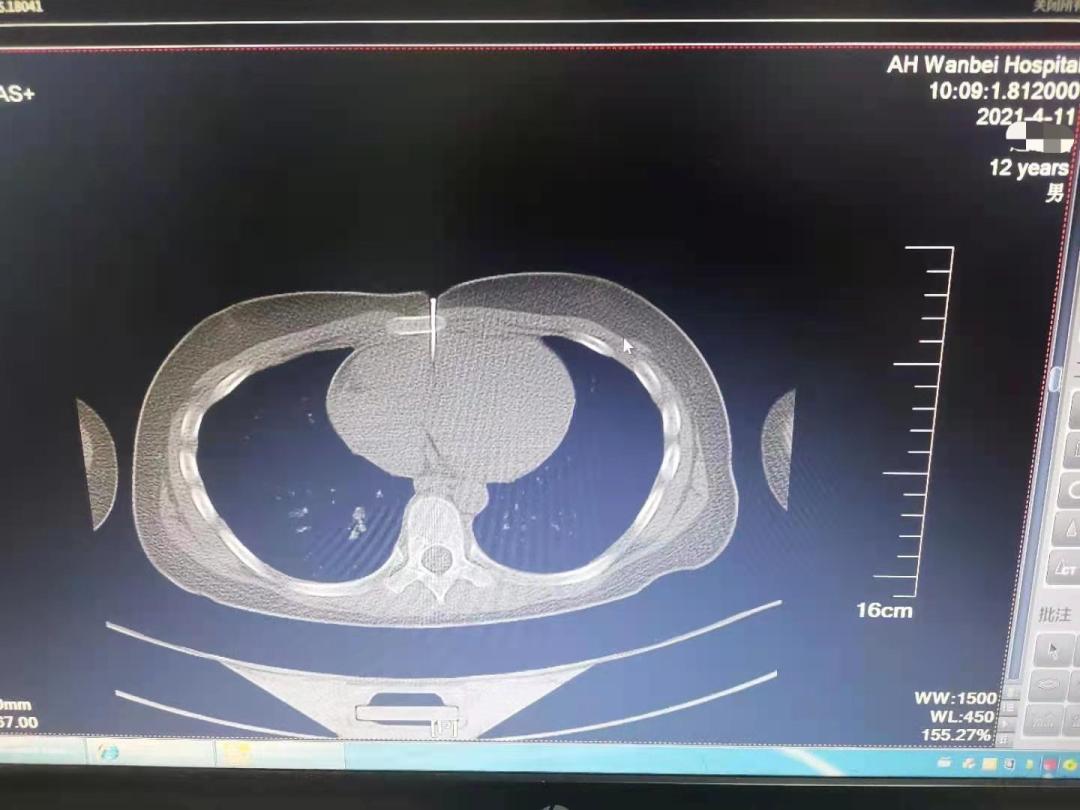

4月11日上午十点左右,宿州市的12岁男孩畅畅(化名)在家玩耍时,不慎被装修用的气钉枪击中胸部。长约4CM的钉子,穿透胸骨,直达心脏!

记者从安医大一附院获悉,该院高新院区紧急开辟绿色通道,心脏大血管外科团队、手术室、麻醉科迅速准备,经过2个小时的手术,钉子被顺利取出,破损的心脏也修补完好,畅畅转危为安。

据畅畅的家人介绍,当天上午家中正在装修,畅畅自己在旁边玩耍。听到叫声赶来才发现孩子误将气钉枪当玩具枪对着自己,触发了扳机,钉子已经穿透皮肤深入到体内。家人立刻将其送入当地医院,后直接转到安医大一附院急诊手术。

据安医大一附院心外科副主任医师龚文辉介绍,钉子根部都深入皮内,幸亏来的及时,否则心包填塞会导致心脏骤停。如果气钉打入的位置再高一点,打到主动脉,几乎就来不及医治了。

记者了解到,手术修补好被钉子穿破的心脏,当晚拔除了气管插管,12日早晨畅畅就从监护室返回病房。